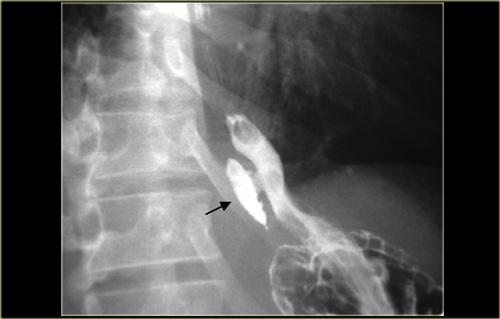

Bên trái là hình ảnh của một nam giới 52 tuổi không có triệu chứng.

Hình chiếu thẳng (AP) và hình chiếu nghiêng cho thấy màng mỏng, ngắn (mũi tên) với mức độ nhô vào lòng ống tối thiểu.

Bên trái là hình ảnh của một phụ nữ 42 tuổi bị khó nuốt do màng thực quản.

Lòng ống bị hẹp > 50%